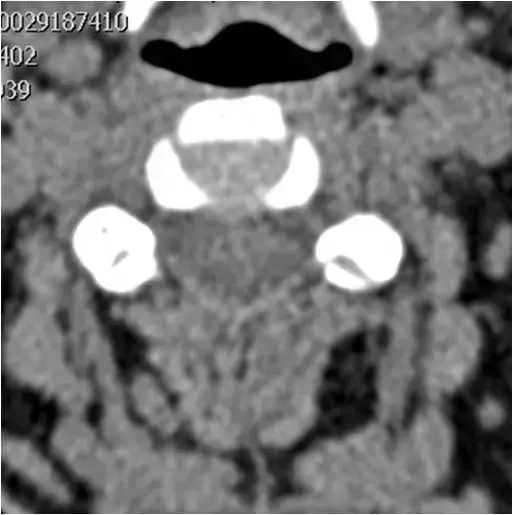

图18:在钩突关节间隙水平处上颈椎的轴向CT图像。